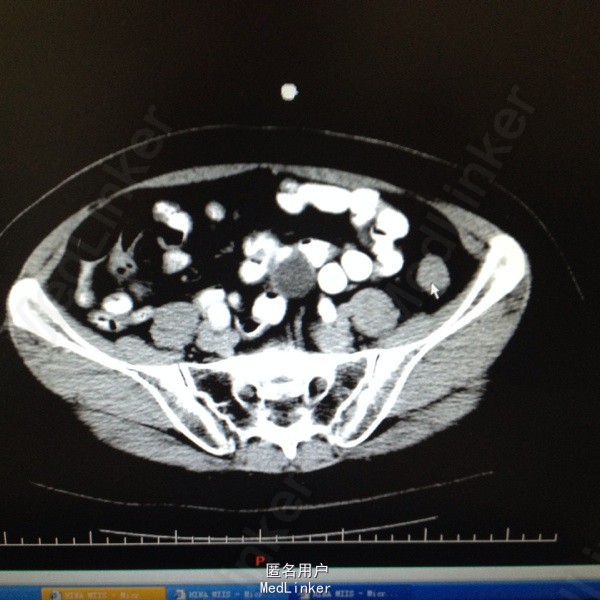

47岁女患。 病史:患者6年前因宫颈癌行全子宫及双侧附件切除。盆腔淋巴结清扫。腹主动脉旁淋巴结活检术。后又行局部放疗。因双肾积水来我科。患者自述平时轻微排尿困难,尿线细。

双肾区无叩击痛,双输尿管走形区无压痛。耻骨上区隆起,叩诊浊音。排尿后留置尿管引流尿液400ml。 辅助检查:肌酐99。 ct:双肾及输尿管积水。 留置尿管后一周泌尿系彩超:双肾积水明显减轻。具体见图片。

诊断:双肾及双输尿管积水 神经源性膀胱 给予患者留置尿管后1周行泌尿系彩超检查肾积水减轻。